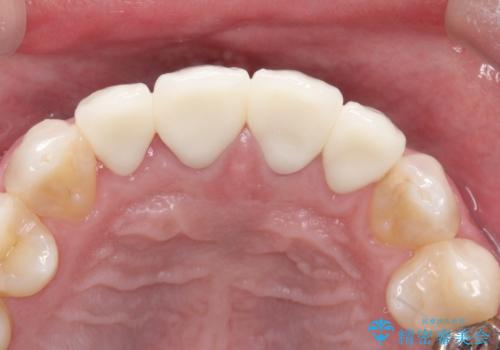

審美的な改善はもちろんのこと、ぴったりとしたものを装着することで、歯茎の発赤も改善されました。